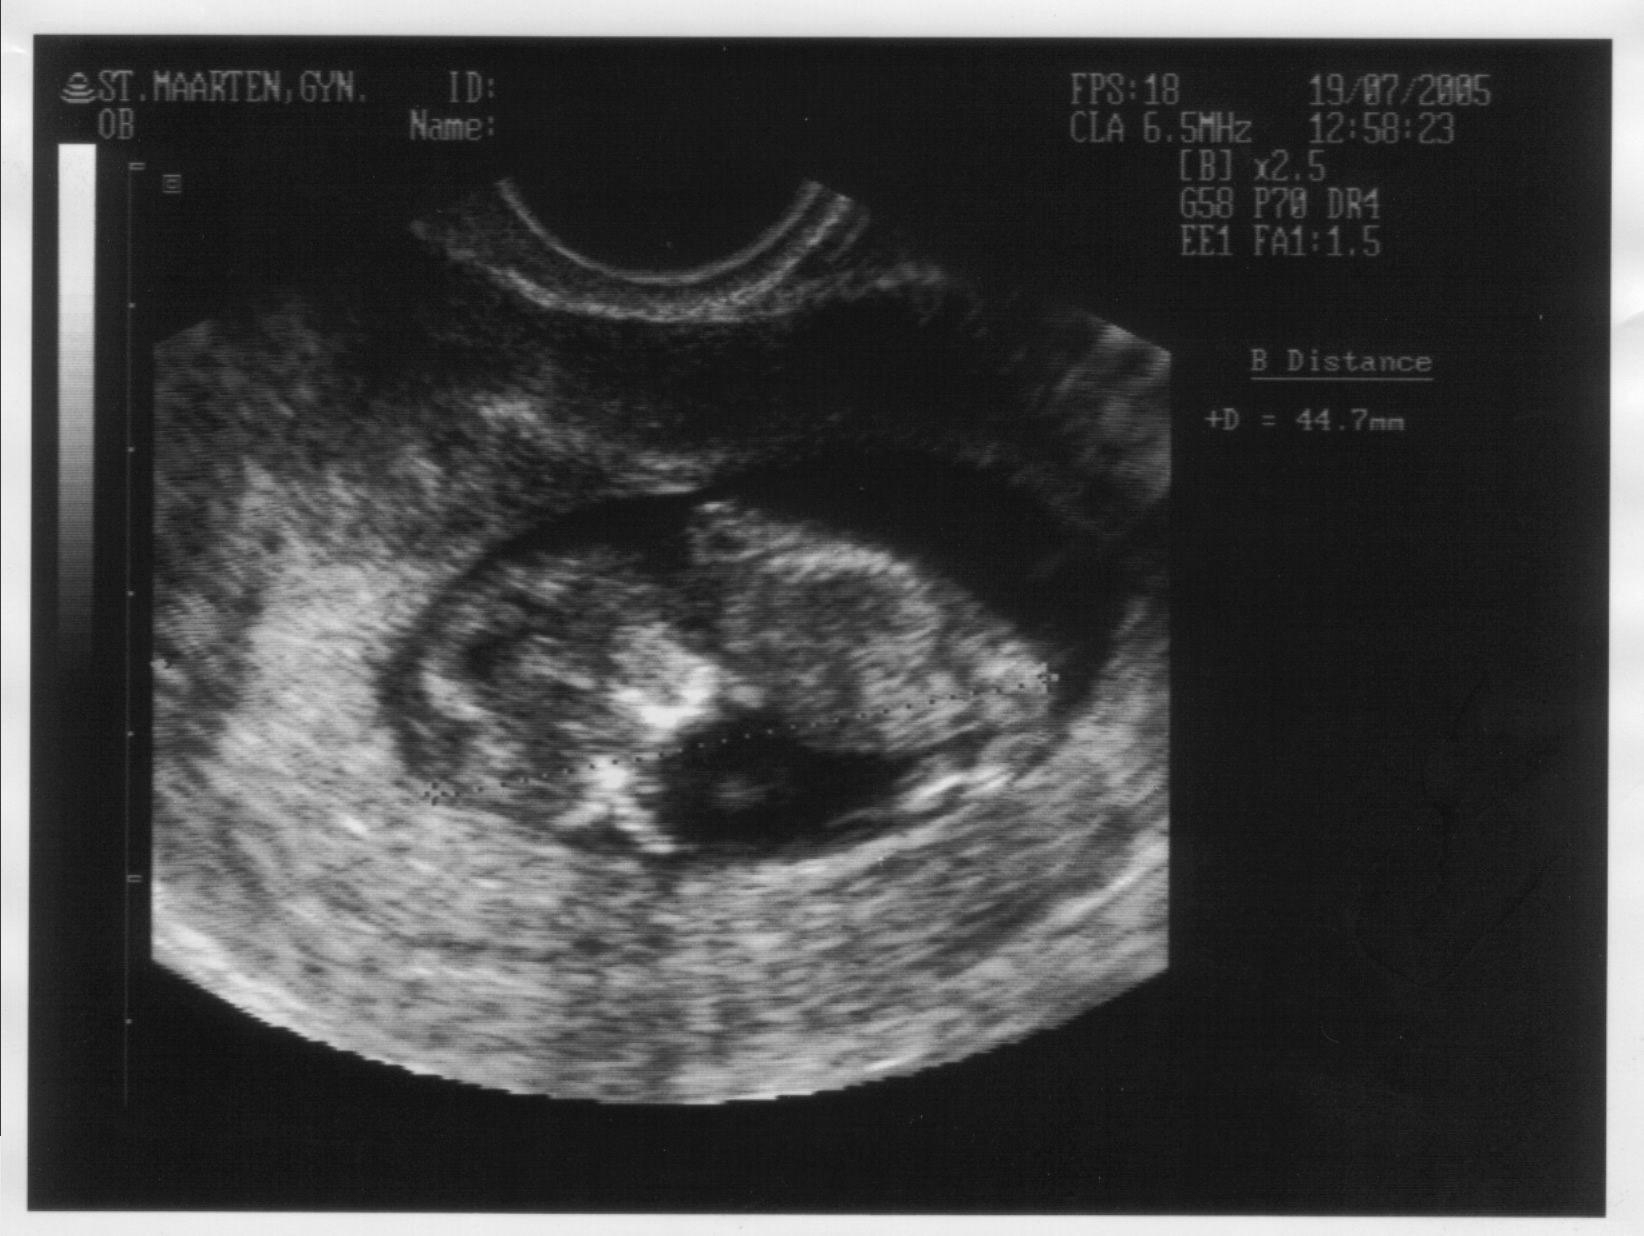

Het lijkt anders op de foto, maar in feite is het lichaampje op 11 weken nog maar 4,5 cm groot